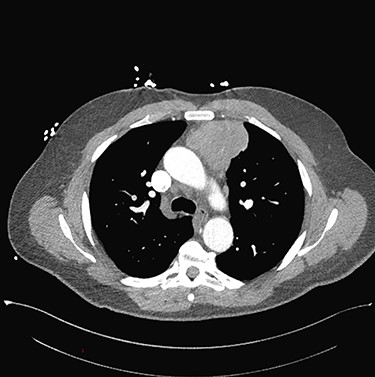

Sixty-three-year-old male was with the history of diabetes and hypertension who presented with 2 days of new onset, intermittent and non-pleuritic left-sided chest pain, with a few months of new onset exertional dyspnea. Chest X-ray showed a convex shaped mass at the left hilum. Chest CT angiography revealed a 5.6 × 7.1 × 5.4 cm hypodense mass in the anterior mediastinum involving the adjacent anterior medial left upper lobe, and adjacent mildly enlarged aorticopulmonary window lymph nodes (Fig. 1). PET scan demonstrated a hypermetabolic anterior mediastinal mass adjacent to medial left upper lobe highly suggestive of malignancy (Fig. 2). Ultrasound-guided core needle biopsy showed nests of small cells with peripheral palisading and focal abrupt transition to squamous cell, consistent with basaloid carcinoma of thymic gland. Immunostainings of the tumor cells were positive for cytokeratin AE1/AE3, cytokeratin CK904, p63 and p40.

Chest CT angiography revealed a 5.6 × 7.1 × 5.4 cm hypodense mass in the anterior mediastinum involving the adjacent anterior medial left upper lobe.